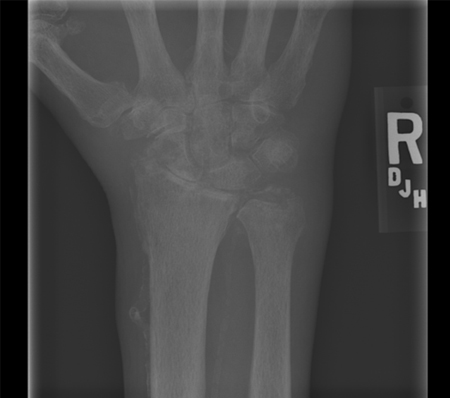

Depósito de pirofosfato de cálcio

Radiografia de punho de paciente com artrite crônica por pirofosfato de cálcio, mostrando alterações degenerativas graves

Da coleção pessoal de Ann K. Rosenthal, MD